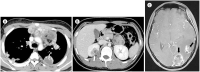

The mediastinum is the most prevalent site of extragonadal teratomas. Patients with mediastinal mature teratomas are usually young adults, and the condition does not show significant sexual differences. Mediastinal teratomas are mostly located in the anterior mediastinum. Patients are usually asymptomatic, although they can have several complications when the teratomas become large or rupture. Most mediastinal teratomas can be diagnosed using CT. Diagnosing ruptured or malignant teratomas is challenging because of their atypical clinical and radiological presentations. In this article, we describe various manifestations of mediastinal teratomas, with an emphasis on radiologic features.